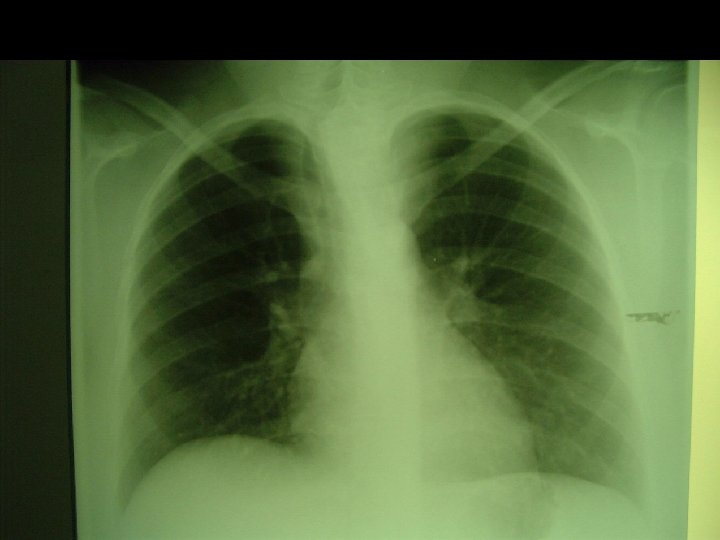

Euthyroid Enlargement • Aetiology: – Iodine deficiency (goitre) – Malignancy • Pre-operative Assessment: – Airway – Retrosternal extension – Laryngeal nerve involvement • esp. with malignant lesions – Risk of hypothyroidism Clinical assessment adequate

Euthyroid Goitre • Anaesthesia: – Intubation – Flexible tube – Anaesthesia usually with controlled ventilation • Coughing • LMA may be adequate – Vocal cord assessment on extubation – Tracheomalacia